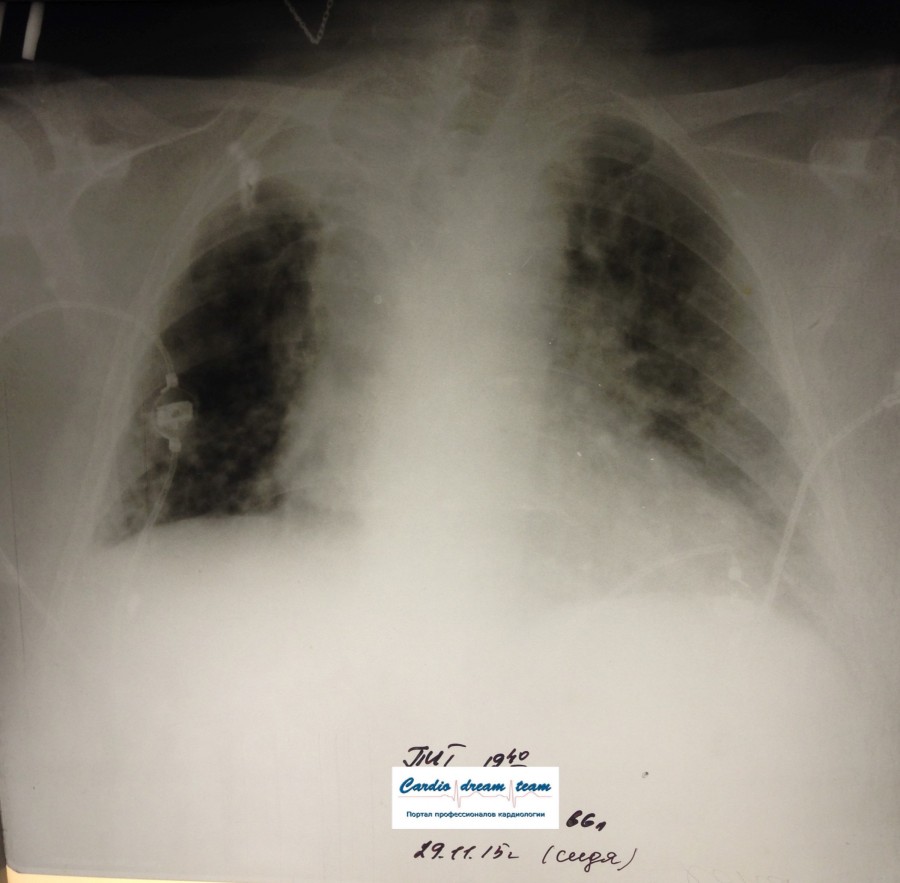

Не обсуждалась Дата 23-ИЮЛ-15 ОПИСАНИЕ: Проведена рентгенография органов грудной клетки в прямой проекции, положение лежа, условия ПИТ Легочные поля: неравномерно прозрачны за счет сосудистого обогащения, в базальных отделах с обеих сторон, отмечается сгущение легочного рисунка, за счет гиповентиляции, в плевральных полостях жидкость Легочный рисунок: Изменен по смешанному типу: обогащен за счет сосудистого компонента, деформирован за счет склероза. Корни: бесструктурны, расширены за счет сосудистого компонента, обогащены Синусы: определяется наличие жидкости по линии 5 ребра Сердце: широко лежит на диафрагме отмечается расширение границ сердечной тени влево, вправо экг-электроды. ЗАКЛЮЧЕНИЕ: Рентген-признаки 2-х стороннего гидроторакса с гиповентиляцией базальных сегментов.. Признаки застоя по МКК 2 степени (умеренно выраженный). Пневмосклероз. Р-признаки гипертрофии левого желудочка сердца. Склероз аорты.